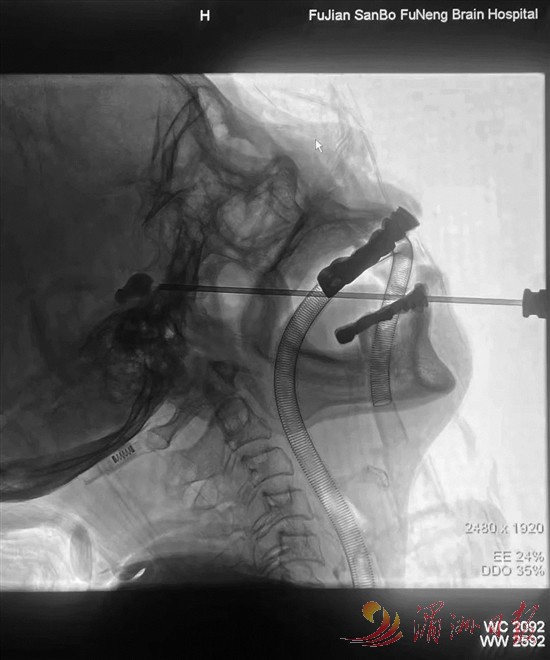

三叉神经痛球囊压迫术

三叉神经痛被称为“天下第一痛”,患者常因剧痛不敢进食、洗脸,甚至丧失生活信心。医院在省内率先引入“三叉神经半月节球囊压迫”技术,以微创方式替代传统的开颅手术破解难题:手术仅需10余分钟,在患者嘴角穿刺针眼大小的创口,用球囊精准压迫痛觉神经,术后即刻缓解疼痛。一位饱受疼痛折磨十余年的李阿姨,术后摸着面颊哽咽道:“张主任的‘神针’,让我重获新生”。